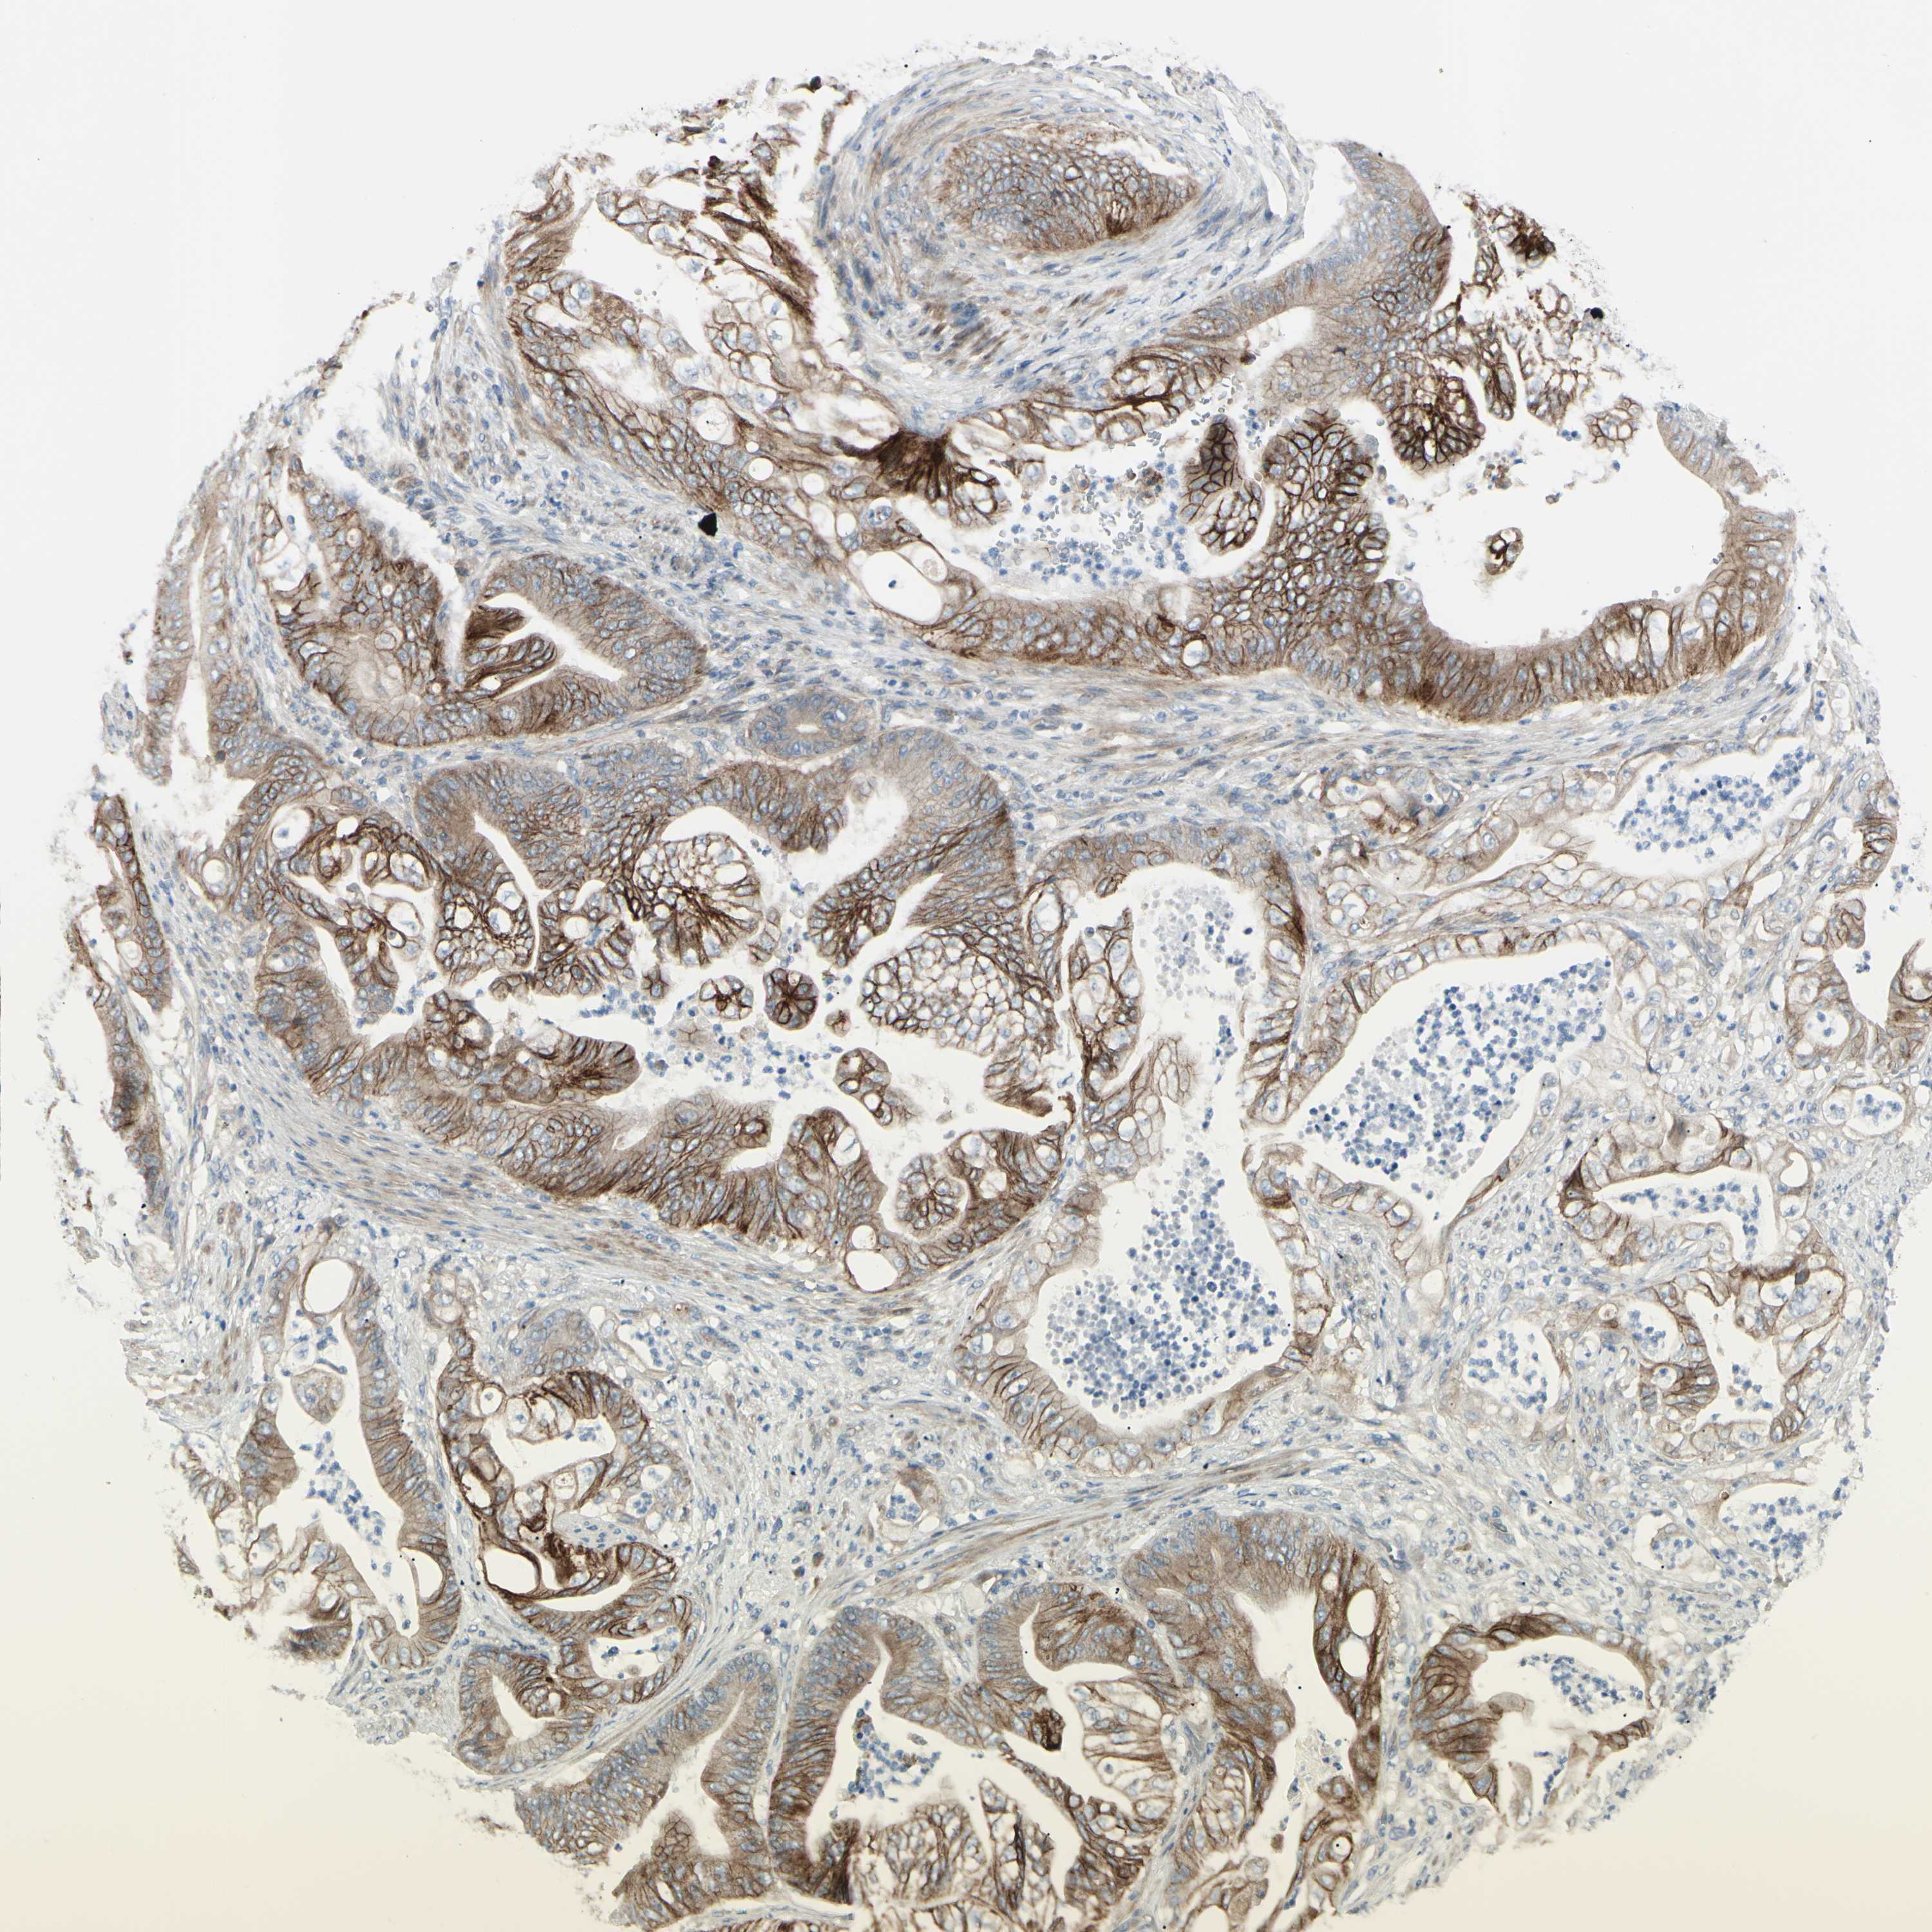

STOMACH CANCER - Protein expressioni

A mouse-over function shows sample information and annotation data. Click on an image to view it in a full screen mode. Samples can be filtered based on level of antibody staining by selecting one or several of the following categories: high, medium, low and not detected. The assay and annotation is described here.

Note that samples used for immunohistochemistry by the Human Protein Atlas do not correspond to samples in the TCGA dataset.

Antibody stainingi

Antibody staining in the annotated cell types in the current human tissue is reported as not detected, low, medium, or high, based on conventional immunohistochemistry profiling in selected tissues. This score is based on the combination of the staining intensity and fraction of stained cells.

Each image is clickable and will lead to virtual microscopy that enables deeper exploration of all samples and also displays staining intensity scores, fraction scores and subcellular localization as well as patient and tissue information for each sample.

Antibody HPA010537

Staining

High

Medium

Low

Not detected

Intensity

Strong

Moderate

Weak

Negative

Quantity

>75%

75%-25%

<25%

None

Location

Nuclear

Cytoplasmic/membranous

Cytoplasmic/membranous,nuclear

Adenocarcinoma, NOS

Adenocarcinoma, High grade